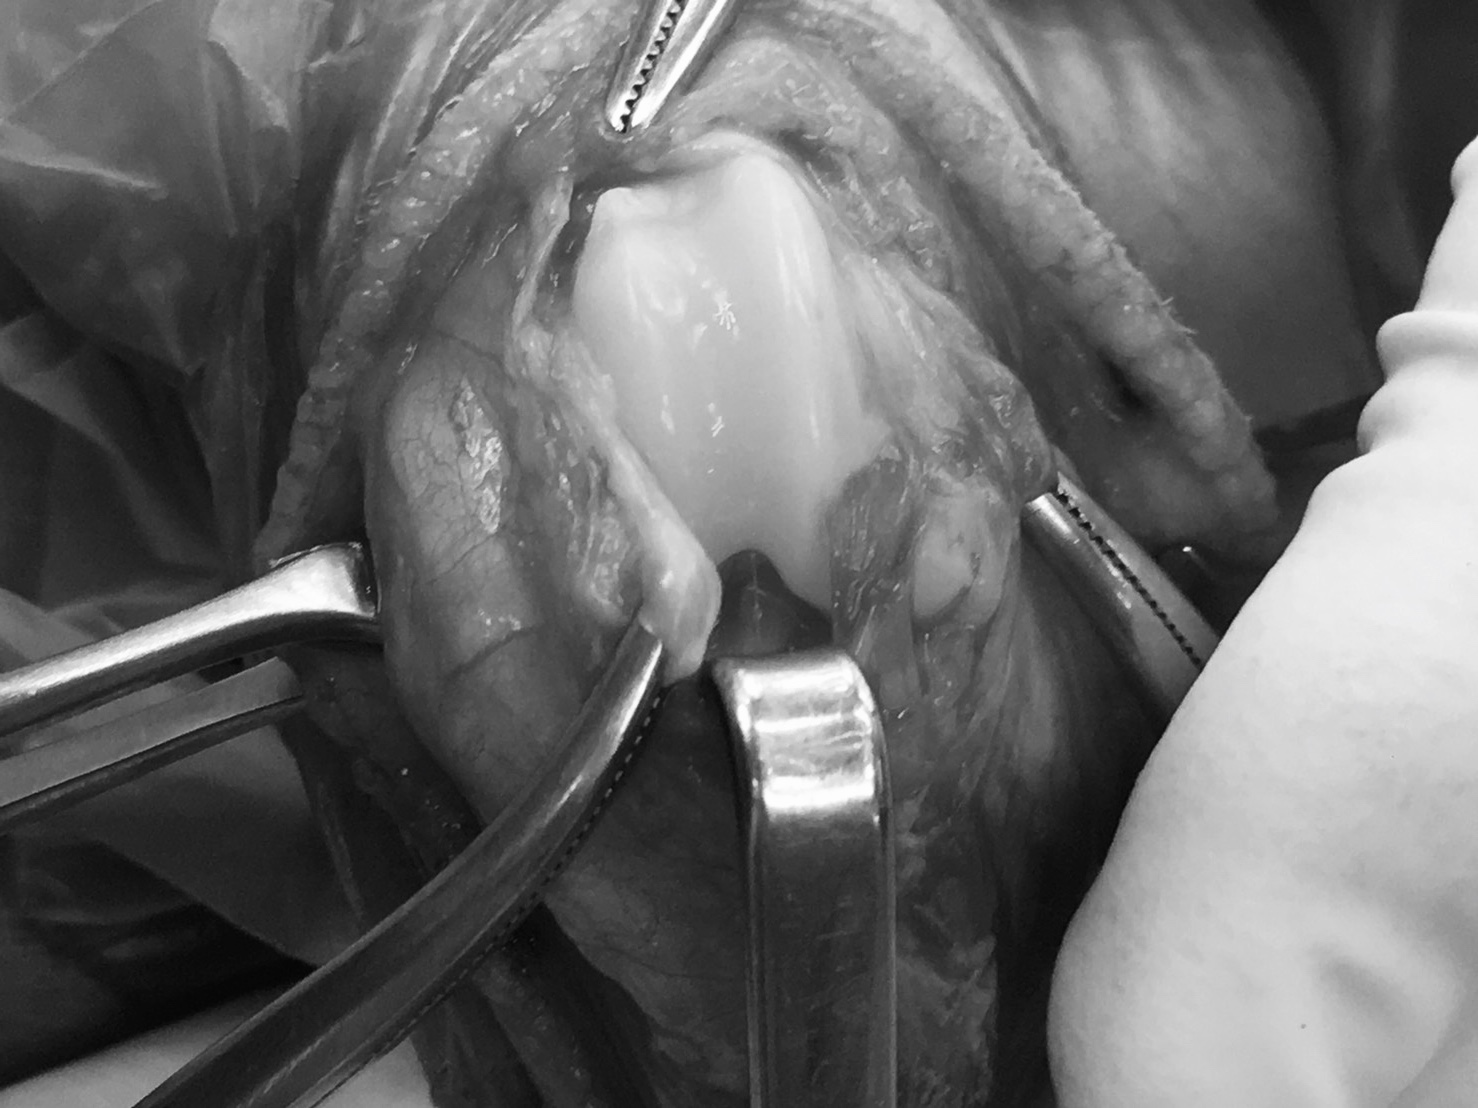

術中の写真です。溝はありますが浅いです。

溝の表面をブロック型に骨切りし、内部を削って深くします。

一度外したブロックの部分を再び戻します。骨切り前に比べて溝が深くなっているのが分かります。